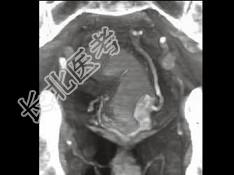

- 单项选择题男,50岁, 血便,大便形状改变, CT如图所示,最可能的诊断是 ( )

A、直肠息肉

B、直肠内粪便

C、直肠癌

D、直肠腺瘤

E、直肠淋巴瘤